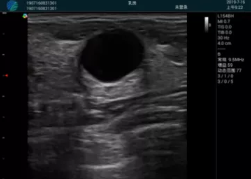

M20查看:囊內回聲均勻,邊界清晰,囊壁光滑

M20引導抽吸術后囊腫消失,原區(qū)域空腔形成,脂肪層與腺體層架構發(fā)生改變